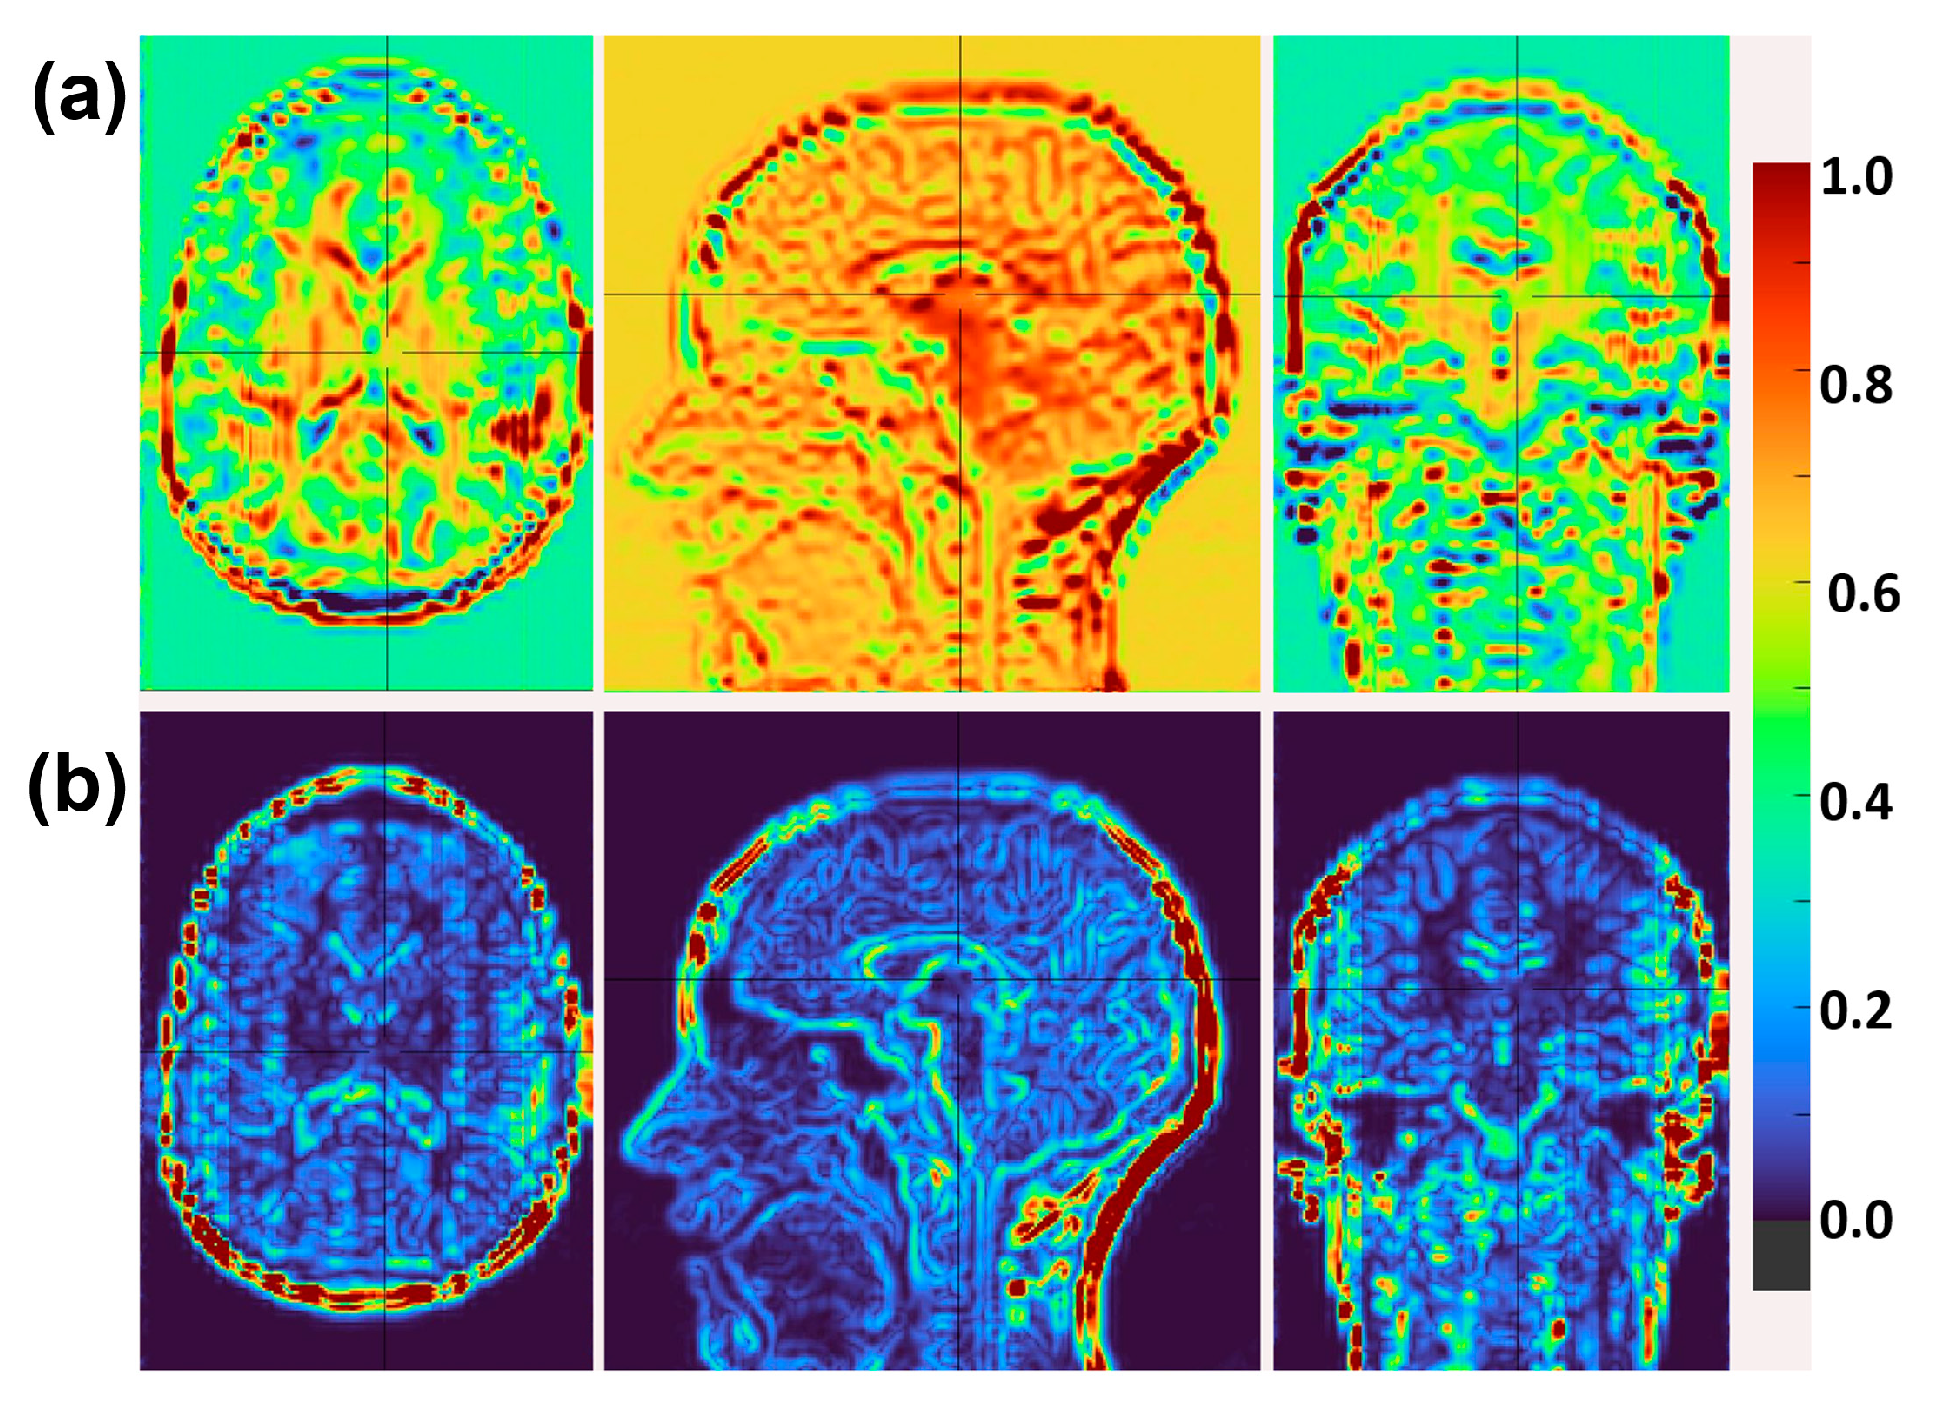

4.3. Cross-Field Validation Using Paired 3T/7T Datasets